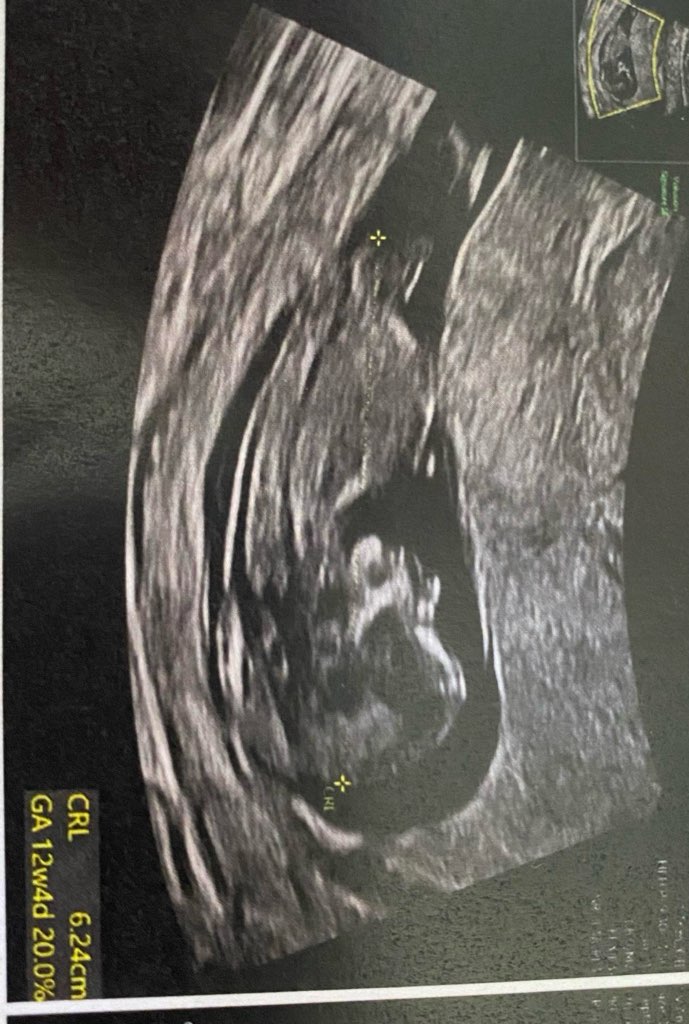

Lekarz stwierdził, ze na 90% dziewczynka. Mam już dwoch chłopaków :) mam o miałam nadzieje na córeczkę

Ocena wyrostka w 12+0 i nawet do 13+ nigdy nie jest na 90% 😉 W 11+ wyrostek w zasadzie u każdego wygląda tak samo, zaczyna się różnicować w 12+, a Ty usg zrobiłaś na samiutkim początku tego tygodnia. Ja taki wyrostek jak Twój miałam w 11+ileś, wg USG 12+2, a tydzień później już zmienił wygląd. Pytanie czy to już właściwy wyrostek, czy jeszcze nie, bo jest dosyć cienki. W mojej ocenie za wcześnie na ocenę w 90% 🤷🏼‍♀️ Można tak dla zabawy sobie oceniać ;) Wszystko jest możliwe na tym etapie :) Z ciekawości możesz sobie skoczyć na usg za tydzień, półtora 🤪